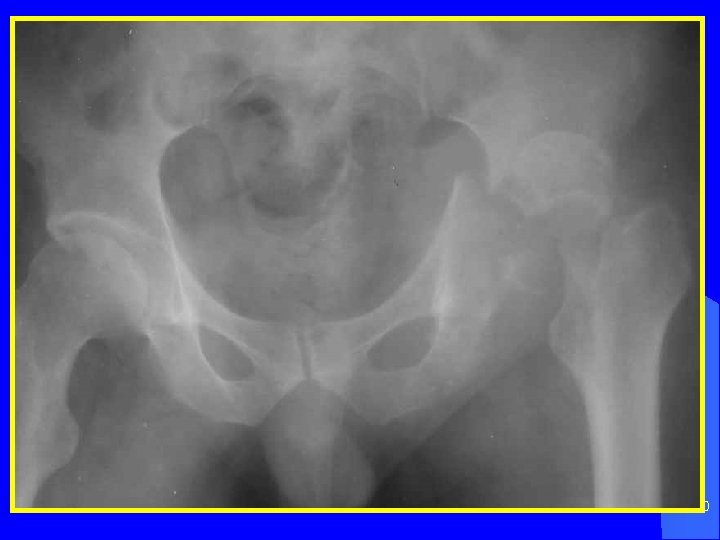

Повреждение костей таза 3

ПОВРЕЖДЕНИЯ КОСТЕЙ ТАЗА Больные с повреждением костей таза составляют от 5 до 10% всех травматологических больных. Среди пострадавших с множественными переломами они составляют 3, 3%, с сочетанными повреждениями 25, 5%. 6

У каждого третьего пострадавшего с этими повреждениями таза возникает травматический шок. При множественных и сочетанных переломах таза массивное кровотечение (до 2, 5 литров крови). Нередко тяжесть клинических проявлений определяется осложнениями, к которым относятся повреждения внутренних органов. 7